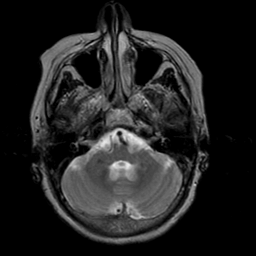

Stroke:T2-weighted MR #2 -- Slice #5

[Home][Help][Clinical] Slice 5